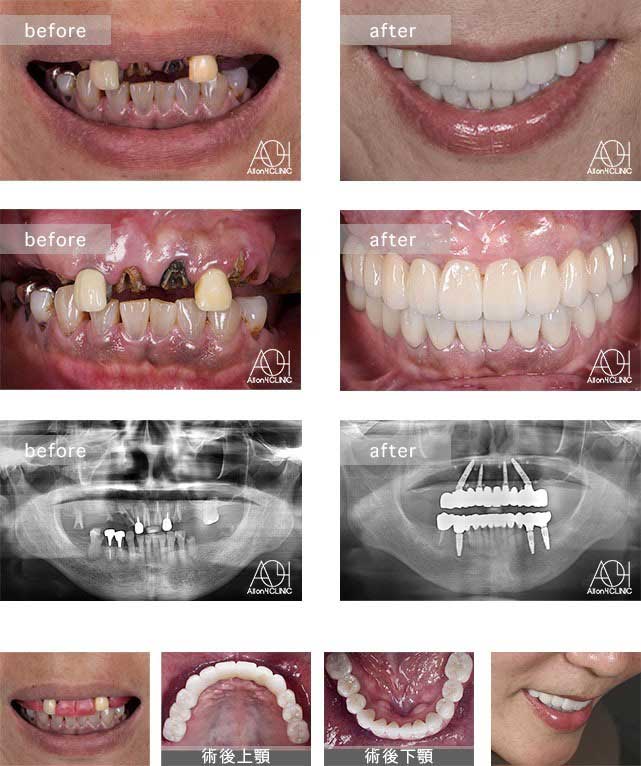

Treatment : All-on-4 zygoma

- Upper All-on-4

- Lower All-on-4

Age : 65 Sex : 男 H.M

| 主訴 | 日本各地のクリニックを受診し、カウンセリングを何回も受けているがどのクリニックで治療を受けるべきか迷っている。 |

| 治療内容 | ガイデッドサージェリーにてインプラント埋入。骨量が少量であったためザイゴマインプラントにて治療 |

| 治療費(総額) | ¥5,200,000(税抜) 『モニター割引適用』 『オリジナル動画撮影協力あり』 |

| リスク | 治療後の口腔管理が不適切な場合、埋入したインプラント周囲に感染・炎症を起こし、脱落する可能性がございます。 |